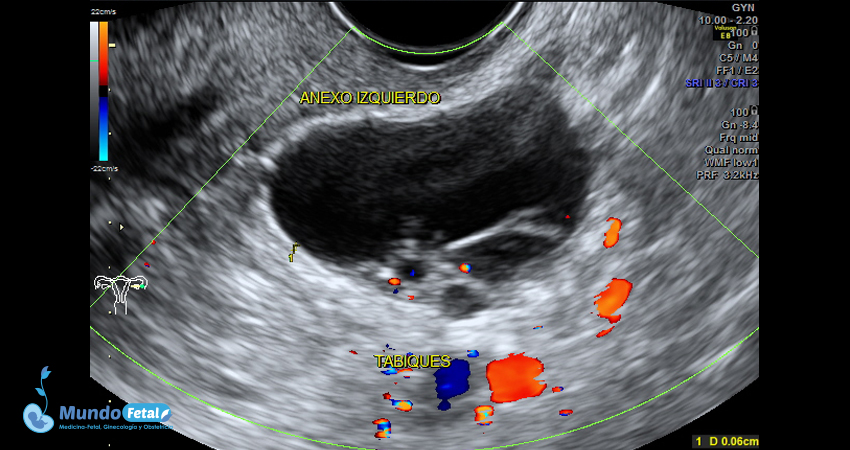

Ultrasonido Pélvico

Estudio anatómico de la región pélvica, que brinda información precisa de (vagina, cérvix, útero, endometrio, trompas de Falopio, ovarios y sus tejidos anexos) de cada uno, descartando alguna complicación de estas estructuras.